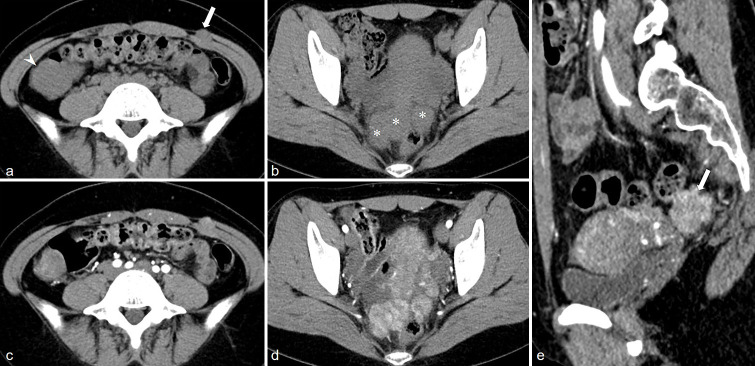

Results: All the 10 LPD patients presented with multifocal lesions in the abdomen and pelvis, and 7 of them had a history of hysteromyoma surgery. The number of lesions was all ≥2, most of them were round or quasi-circular, with clear boundaries and smooth edges, did not invade the neighboring parenchymal organs, with a length of about 1.5~16.8 cm. The lesions were located in the pelvic cavity in 6 cases, the abdominal wall in 6 cases, the intestinal wall in 3 cases, the rectouterine pouch in 1 case, the omentum in 5 cases, the abdominal cavity in 1 case, and the mesentery in 1 case. There were 7 cases with minimal pelvic fluid and 1 case with liver spread. CT showed circular solid nodules with clear boundaries. The density of small lesions was homogeneous. Cystic changes were observed in some large lesions. On MRI, T1-weighted imaging showed hypo to isointense, T2-weighted imaging (T2WI) mostly showed hypointense, and T2WI in some large lesions showed slightly high signal intensity, diffusion-weighted imaging signal intensity was not higher than that of myometrium, apparent diffusion coefficient showed isointense, and solid components of the lesions were significantly more homogeneous enhanced after enhancement, and the enhancement degree was similar to that of normal myometrium.